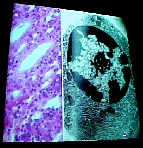

| 6) Kidney using a Light microscope; Plasma cell with an EM ( notice resolution) |